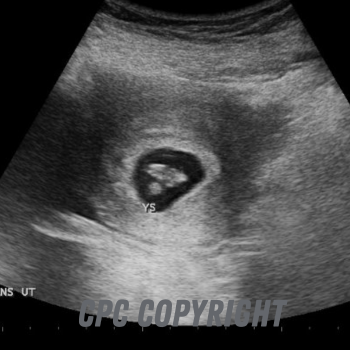

30 days from conception/6 weeks from your last period

4 ½ weeks after conception: Baby grows rapidly for the next few weeks, and will be much easier to see mid-way through the 6th week. Here is a baby about 30 days after conception.